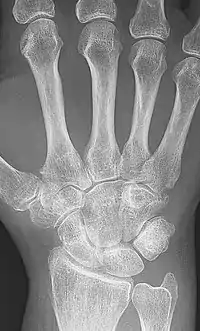

X-ray of the hand in rheumatoid arthritis

X-rays of the hands and feet are generally performed when many joints affected. In RA, there may be no changes in the early stages of the disease or the x-ray may show osteopenia near the joint, soft tissue swelling, and a smaller than normal joint space. As the disease advances, there may be bony erosions and subluxation. Other medical imaging techniques such as magnetic resonance imaging (MRI) and ultrasound are also used in RA.[20][68]